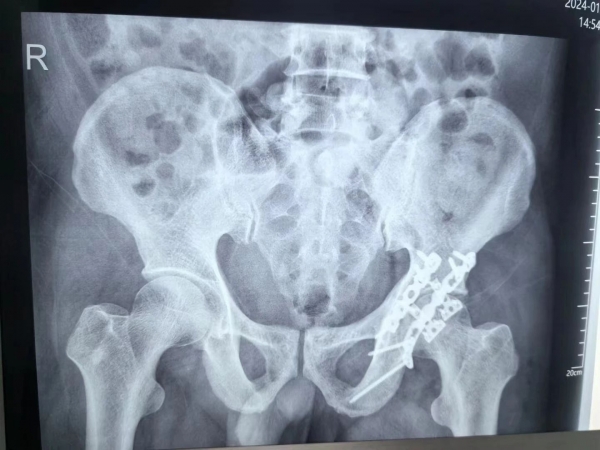

941 瀏覽“燕主任,你看,我能下獨(dú)立走了,走得還挺穩(wěn)的,謝謝了”,已出院的應(yīng)大爺在視頻里露出燦爛的笑容,激動(dòng)地向燕主任發(fā)來(lái)康復(fù)的喜訊?!安焕⑹枪强茖<?,這樣難度的手術(shù),學(xué)到了”,外一科的醫(yī)生邊看視頻邊感慨到。

“外一科有燕主任在,是我們的榮幸,是患者的福音啊”,行政主任丁廣甫總這樣提到。這位肩挑重任,以仁心撐起“生命支柱”的燕主任就是骨科專家創(chuàng)傷主任燕冰。